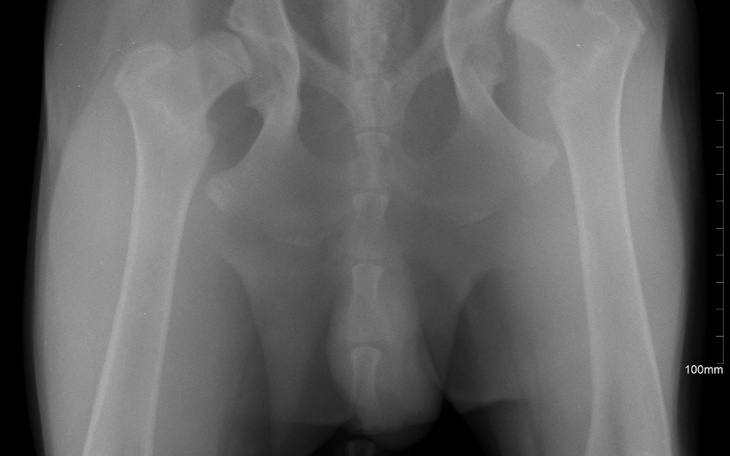

Witajcie, mam psa Karo, ma 8 miesięcy i wykryto u niego dysplazję stawów biodrowych. Jeśli nie zostanie poddany operacji wszczepienia sztucznych panewek stawów to będzie skazany na wózek przyczepiony do tylnych nóg. Jest to młody piesek i chętny do zabaw, biegania, a wózek ograniczy mu to lub uniemożliwi. Bardzo go kocham, jest inteligentny, mądry i nie wyobrażam sobie życia bez niego na emeryturze, na której jestem od kilku miesięcy. Chciałam, żeby był moim przyjacielem , ale bardzo martwię się o niego. Nie wiem czy zdołam opiekować się niepełnosprawnym psem w tym wieku. Bardzo chcę go uratować i proszę o wsparcie nawet w najmniejszej kwocie, którą możecie przekazać bezinteresownie. Jestem wdzięczna za każdą złotówkę i dziękuję z całego serca. Pozdrawiam i dziękuję.